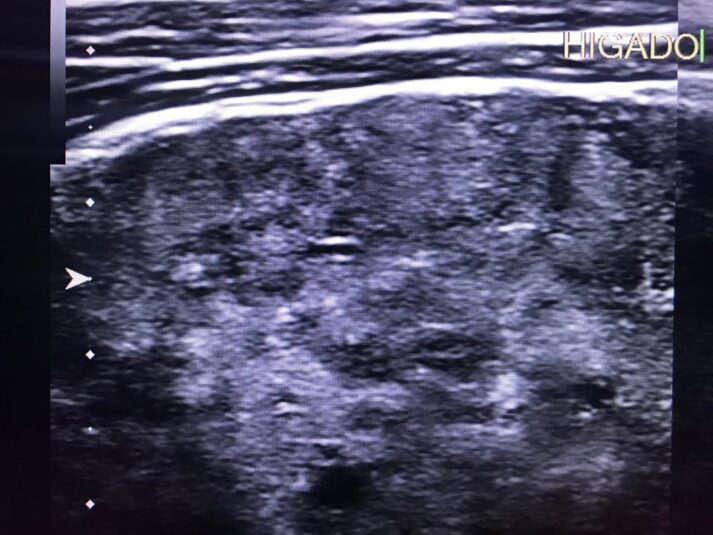

Masculino de 52 años, con cirrosis hepática. La elastografía ecográfica evidencia fibrosis Categoría F3 según escala de METAVIR y la presencia de múltiples nodulaciones, que en su mayoría son menores a 2 cm.